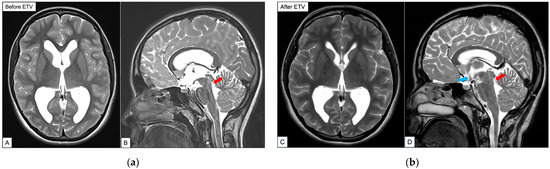

Hyponatremia Following Endoscopic Third Ventriculostomy in an Adolescent with an Aqueductal Web: A Case Report

by Tingting Feng, Lee Ping Ng, Wan Tew Seow and Sharon Y. Y. Low

Reports 2026, 9(2), 122; https://doi.org/10.3390/reports9020122 - 17 Apr 2026

Background and Clinical Significance: Endoscopic third ventriculostomy (ETV) is a well-established cerebrospinal fluid (CSF) diversion technique for treating obstructive hydrocephalus. Here, the complication of post-ETV hyponatremia is rare. Separately, aqueductal web as a cause of obstructive hydrocephalus is also an uncommon occurrence. We [...] Read more.

Background and Clinical Significance: Endoscopic third ventriculostomy (ETV) is a well-established cerebrospinal fluid (CSF) diversion technique for treating obstructive hydrocephalus. Here, the complication of post-ETV hyponatremia is rare. Separately, aqueductal web as a cause of obstructive hydrocephalus is also an uncommon occurrence. We present an unusual case of an adolescent who presented with late symptoms of obstructive hydrocephalus secondary to an aqueductal web and developed a delayed onset of post-operative hyponatremia after a successful ETV procedure. Pertinent aspects of the case are discussed in corroboration with the recent literature. Case Presentation: A previously well 14 year old presented with symptoms of raised intracranial pressure. Neuroimaging demonstrated progressively enlarging ventricles associated with an aqueductal web. She underwent an uneventful ETV and was discharged home. However, she was readmitted for symptomatic hyponatremia that was investigated and most likely attributed to Syndrome of Inappropriate Antidiuretic Hormone Secretion (SIADH). She was managed with fluid restriction with good clinical improvement. Conclusions: We herein report a case of delayed onset of obstructive hydrocephalus secondary to an aqueductal web, treatment challenges faced and the patient’s unexpected occurrence of hyponatremia after a technically successful ETV. This emphasizes that clinicians need to be mindful of this potential post-operative complication and the ability to discern subtle symptoms in a patient whose clinical signs may not be straightforward. Full article